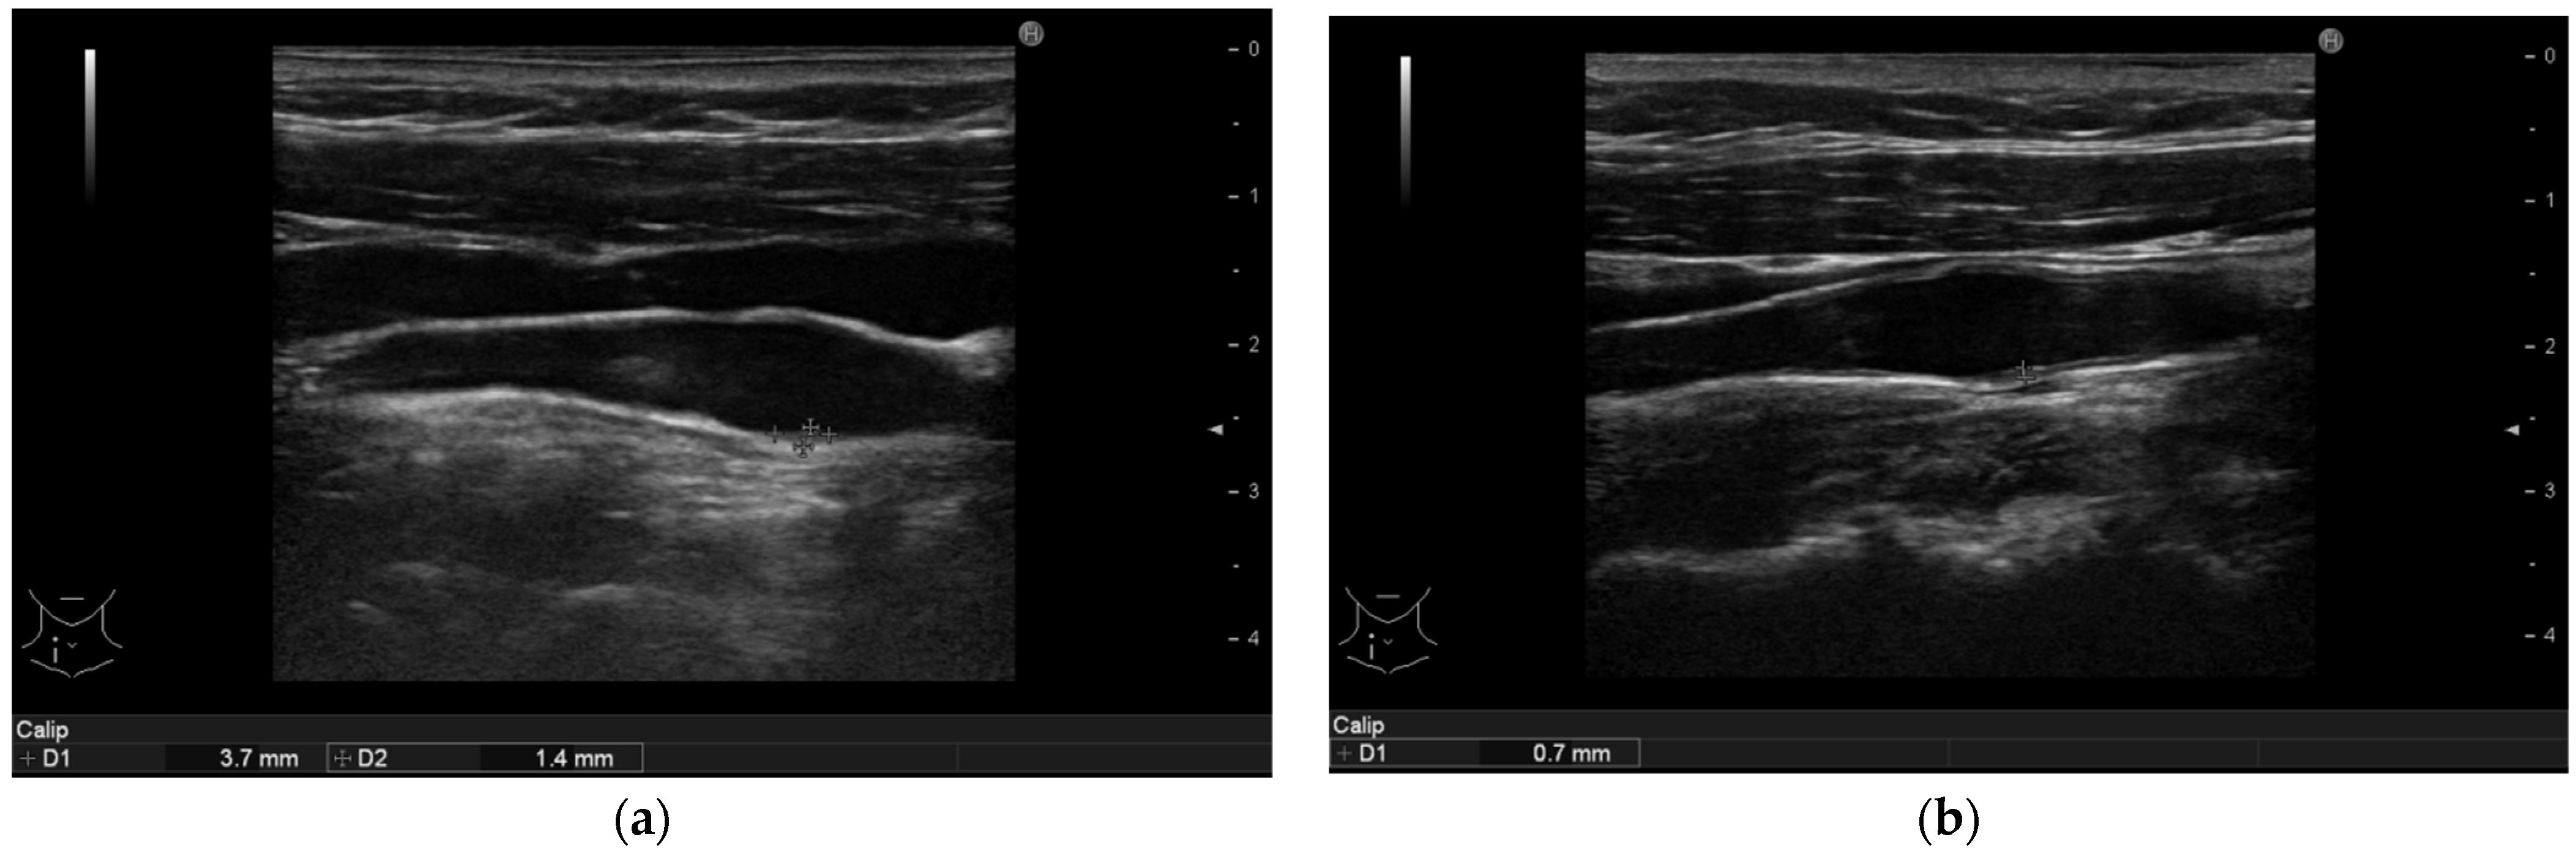

3.4. Ultrasonographic Findings

| Intima media thickness of the right femoral arteries (mm) | 0.9 (0.8–1.05) | 0.7 (0.5–0.9) | <0.001 |

| Intima media thickness of the left femoral arteries (mm) | 0.8 (0.6–1.1) | 0.7 (0.5–0.8) | <0.001 |

| Cumulative area of the non-calcified plaques in all arteries (mm2) | 3.0 (1.8–6.4) | 1.6 (1.1–7.5) | 0.062 |